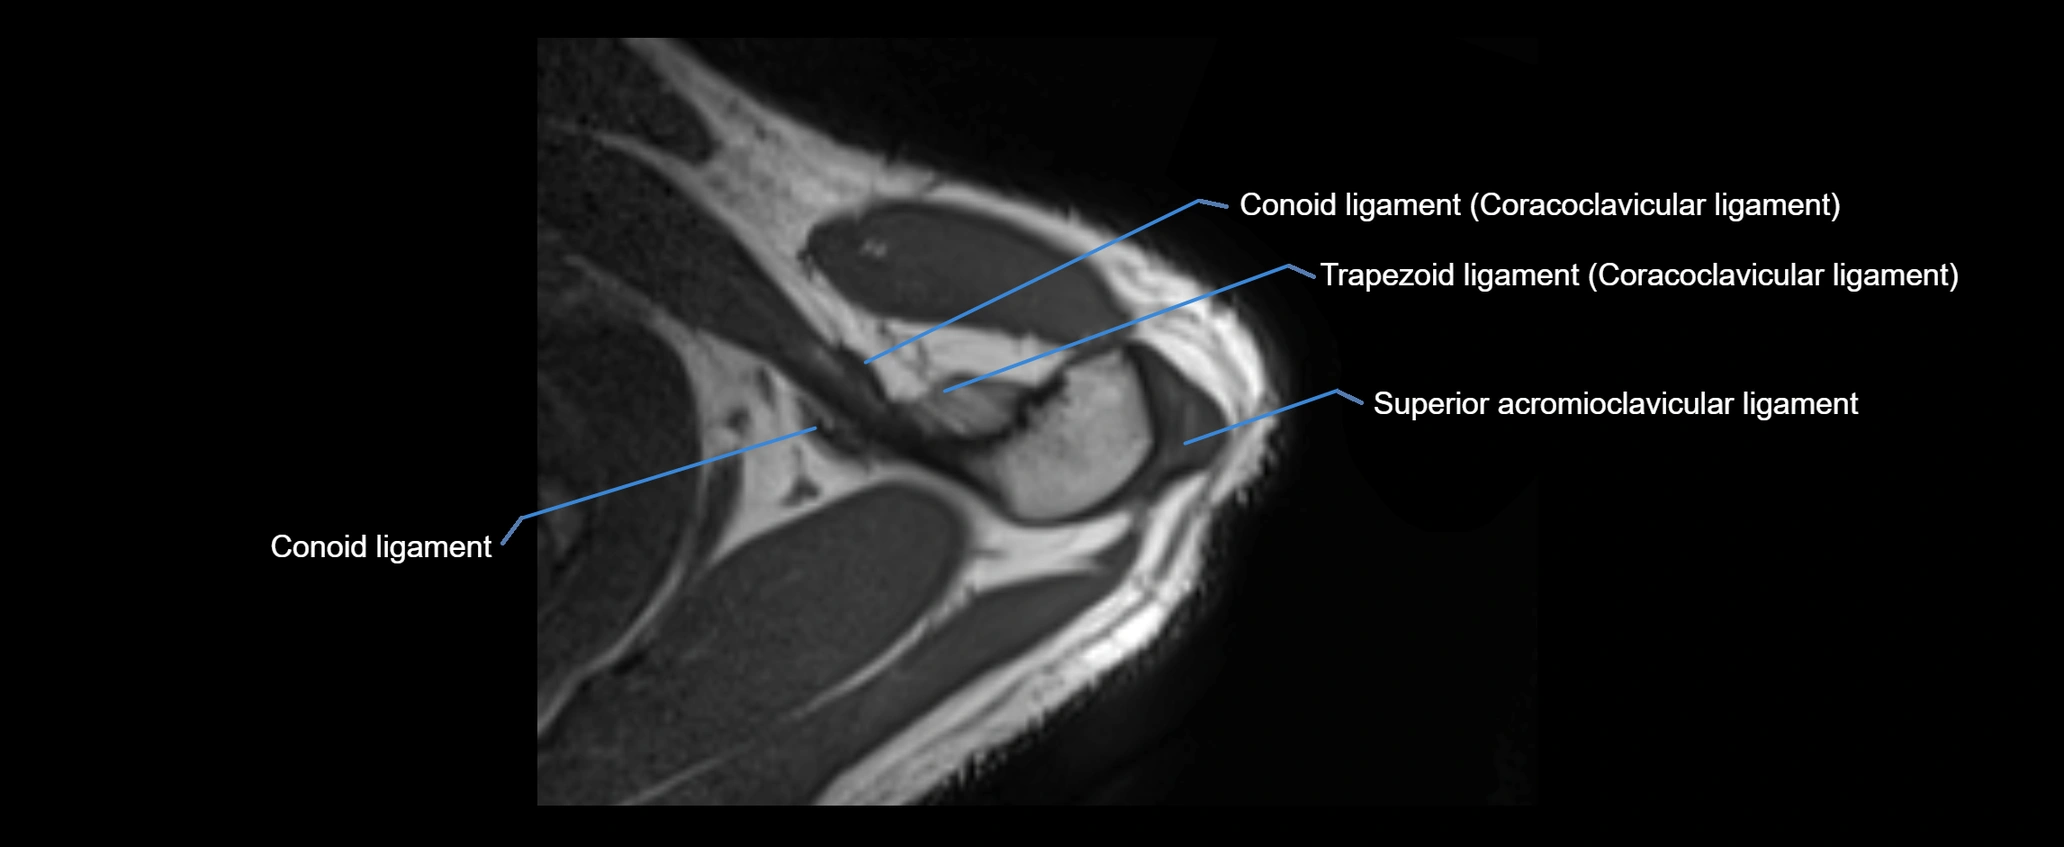

CT image

image